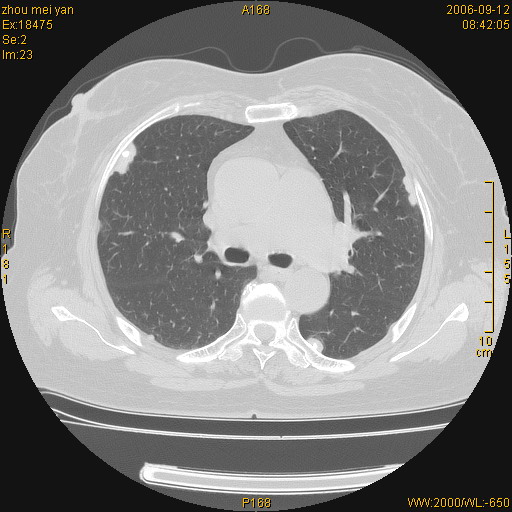

患者、女、55岁。因心率失常住院检查ct发现胸部多发结节。腹部b超肝、胆、胰、脾、肾、子宫附件未见异常。无结核病史,无粉尘接触史。请大家来会诊。谢谢!

病变位于胸膜,多发结节,边界清楚,内见小结节状钙化。其它未见异常。

双侧胸膜多发结节,形态不规则,边缘较清楚,每一个结节中心似乎都有钙化点的特征,与胸膜广基相切。临床无结核病史,无粉尘接触史。

胸膜间皮瘤可能性大。在气管隆突前可见一肿大淋巴结影。

影像表现十分有特点:双侧肋胸膜及膈胸膜广泛散在分布大小在2至6mm左右,较大病灶中心可见钙化。

双侧肋胸膜及膈胸膜广泛散在分布大小不等结节影,较大病灶中心可见钙化。